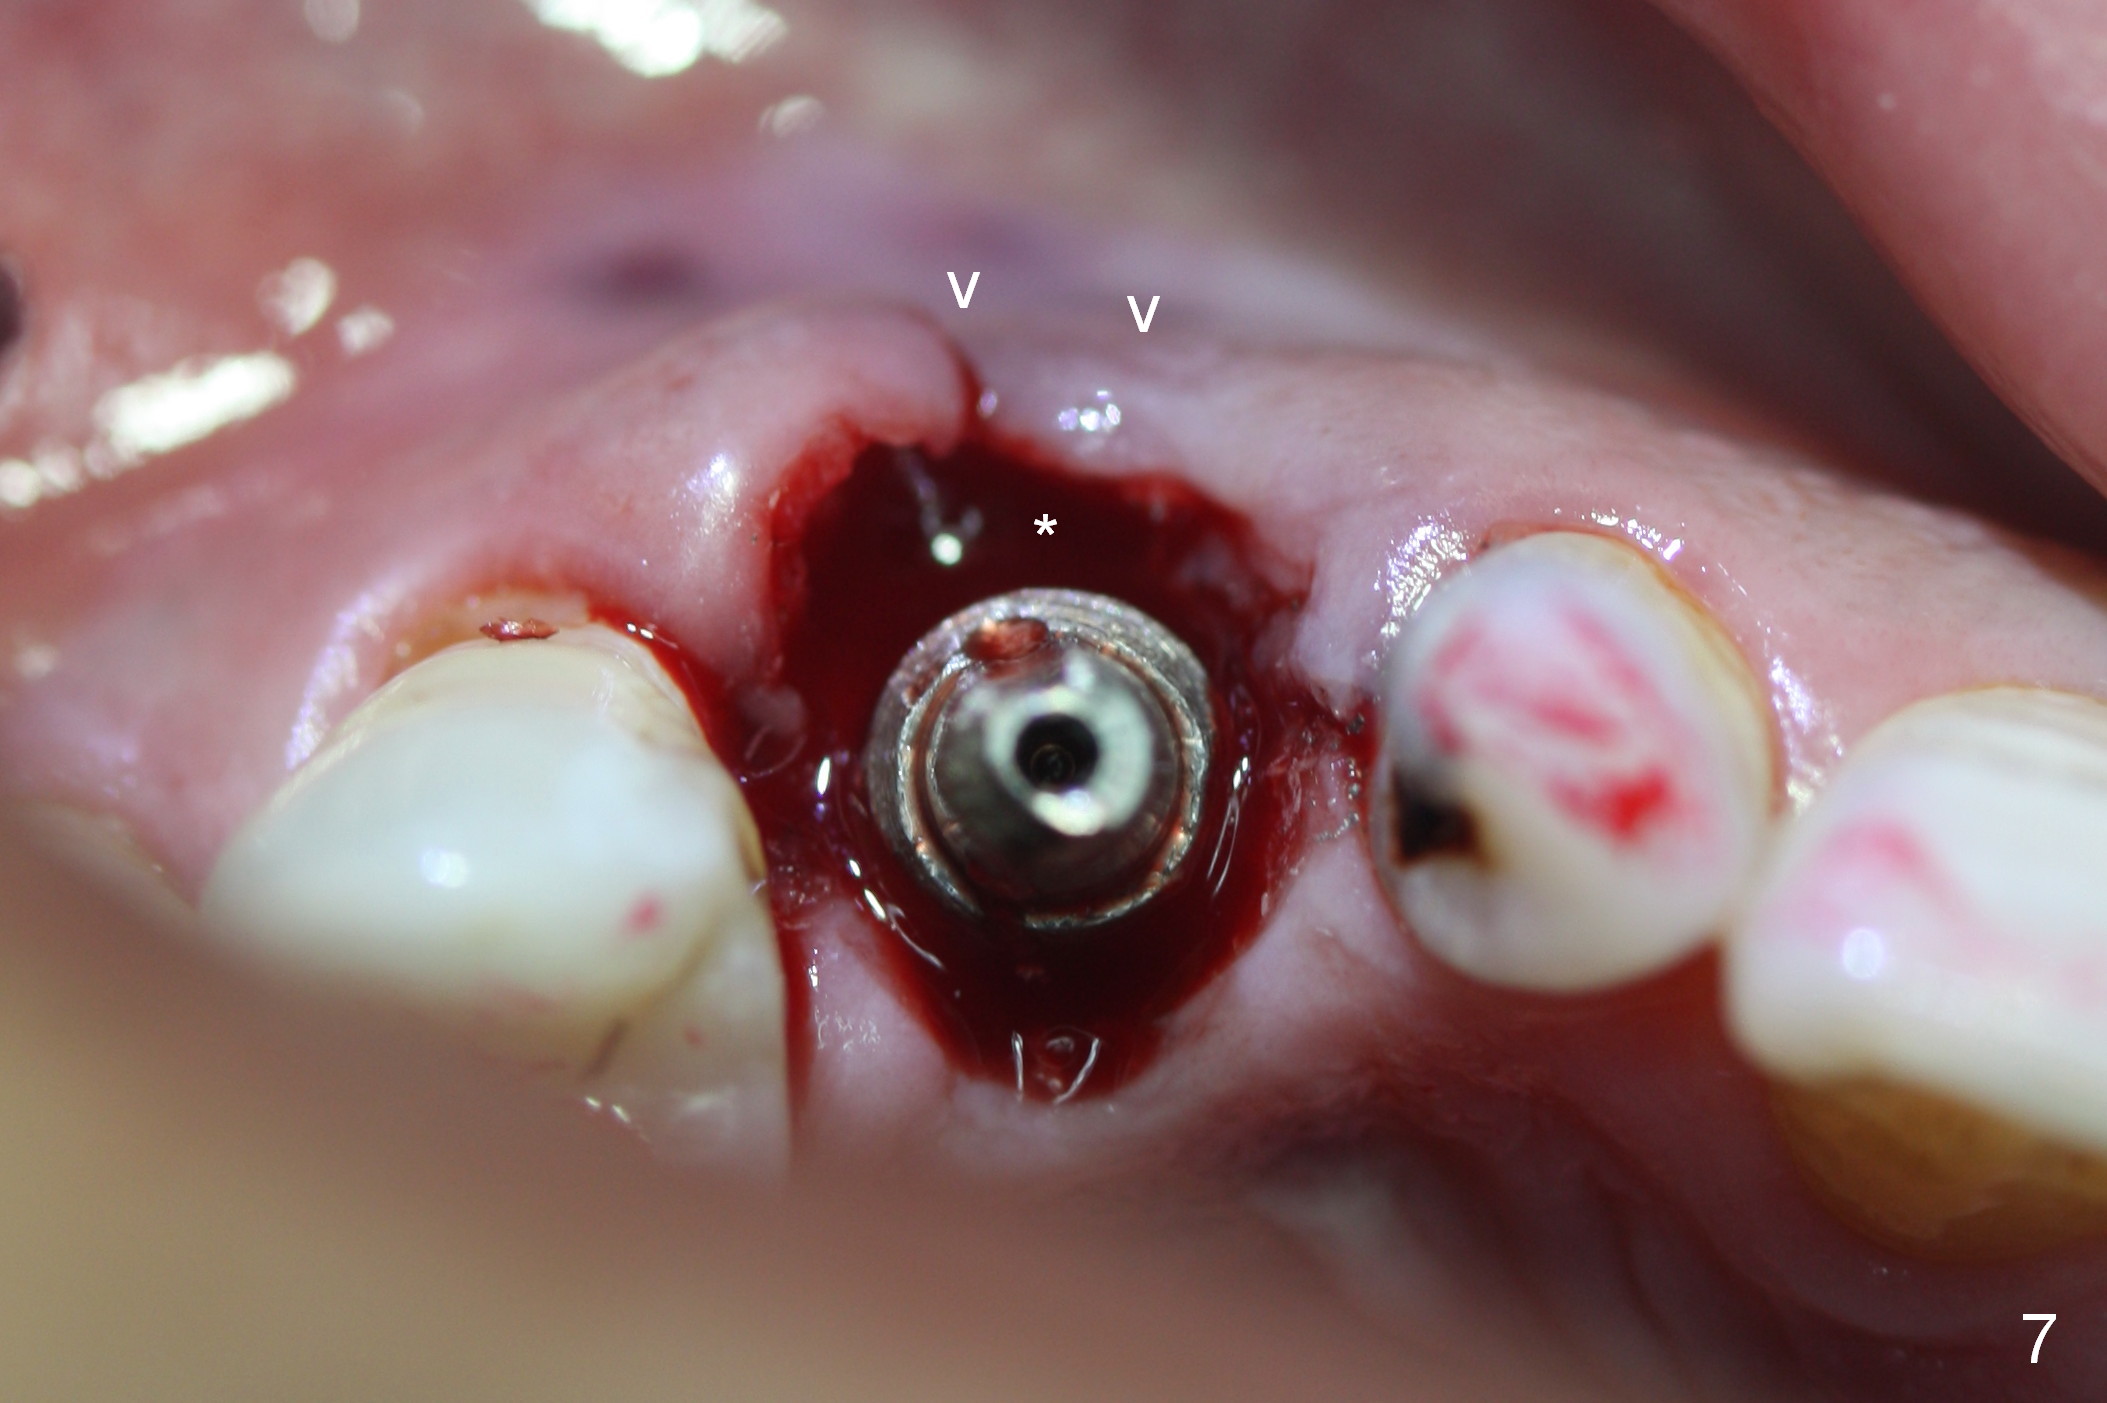

After 5x20 mm implant is placed, the distal gap is filled with bone graft (Fig.5 *). An abutment is placed (A) for fabrication of an immediate provisional (Fig.6 P). The latter hold the labial gingiva bulging (Fig.6 >). When the provisional is removed for bone grafting, the labial gingiva collapses (Fig.7 arrowheads). In fact a piece of cone-shaped Osteotape (Impladent) is placed palatal to the labial gingiva/thin labial plate and a small amount of graft is placed in the deepest area of the socket (labial to the osteotomy) prior to placement of the implant. More graft is placed in the peri-implant gap, particularly labially to keep the labial gingiva convex (Fig.8 arrowheads). The lacerated gingiva is to be approximated with perio glue (Fig.9 <). Collagen dressing is placed over the exposed graft before cementation of the provisional. Perio dressing is applied for further protection and seal.